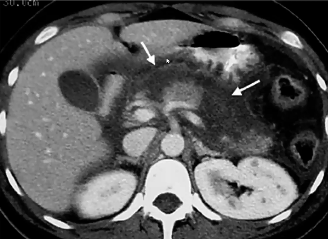

ct scan abdomen and acute panc

estimates severity and prognosis

complications → phlegmons, abscesses, pseudocysts. 2-3 wks after acute pancreatitis